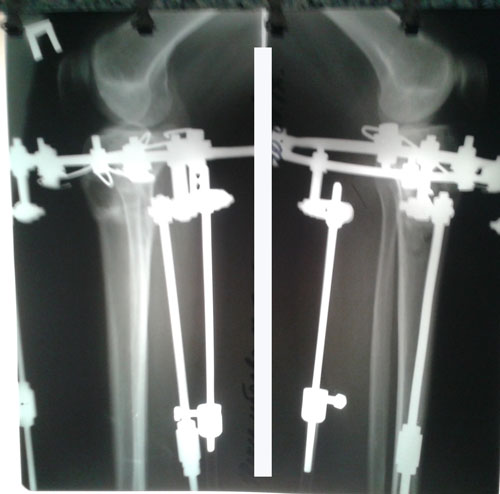

На сращении.

IMG-20170530-WA0005.jpg

Дата операции - 26.04.2017г.

Дата снятия аппаратов 12.07.2017г.

Срок лечения 76 дней.

РЕНТГЕН ПЕРЕД СНЯТИЕМ АППАРАТОВ